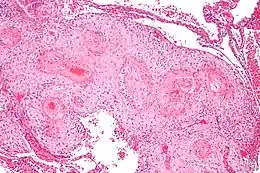

Coupe microscopique montrant la vasculopathie déciduale, corrélat morphologique à l'hypertension artérielle gravidique. Coloration à l'hématoxyline et à l'éosine.